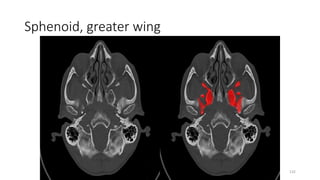

Sphenoid, greater wing

GREATER WING SPHENOID